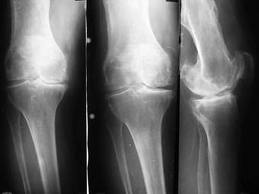

Рентгенография коленного сустава диагностирует переломы, вдавления и трещины, сужение суставной щели, субхондральный остеосклероз, остеофиты характерные для II– III стадии болезни. Кистозная перестройка в эпифизах суставных поверхностей выражена не всегда, даже при тяжелых клинических формах данной локализации. Эта диагностическая процедура проводится в прямой и боковой проекции, а так же в различных специфических укладках.

В зависимости от преимущественной локализации дегенеративно-дистрофического процесса выделяют 4 формы гонартроза:

1. с преимущественным поражением внутреннего отдела коленного сустава (ведущий симптомокомплекс – варусная деформация нижней конечности с вершиной в области коленного сустава;

2. с преимущественным поражением наружного отдела (вальгусная деформация);

3. деформирующий артроз пателло-феморального сочленения;

4. гонартроз с поражением всех отделов сустава.